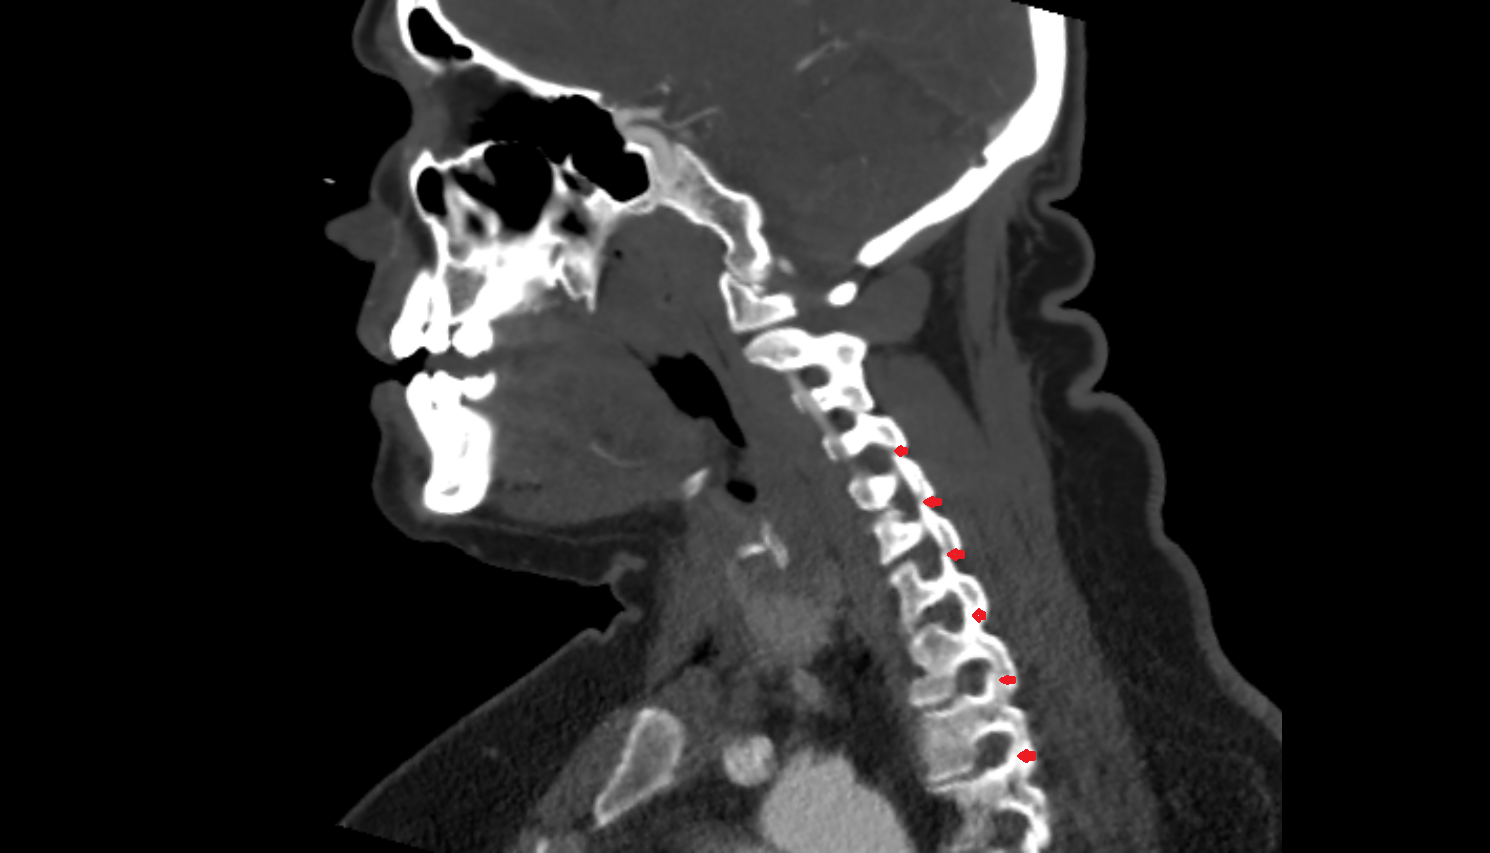

- C3–C4 intervertebral disc

- Anulus fibrosus of intervertebral disc

- Nucleus pulposus of intervertebral disc

- Facet joint of vertebra (Zygapophyseal joints)

- Anterior longitudinal ligament

- Posterior longitudinal ligament

- Ligamenta flava (Ligamentum flavum)

- Intervertebral Disc